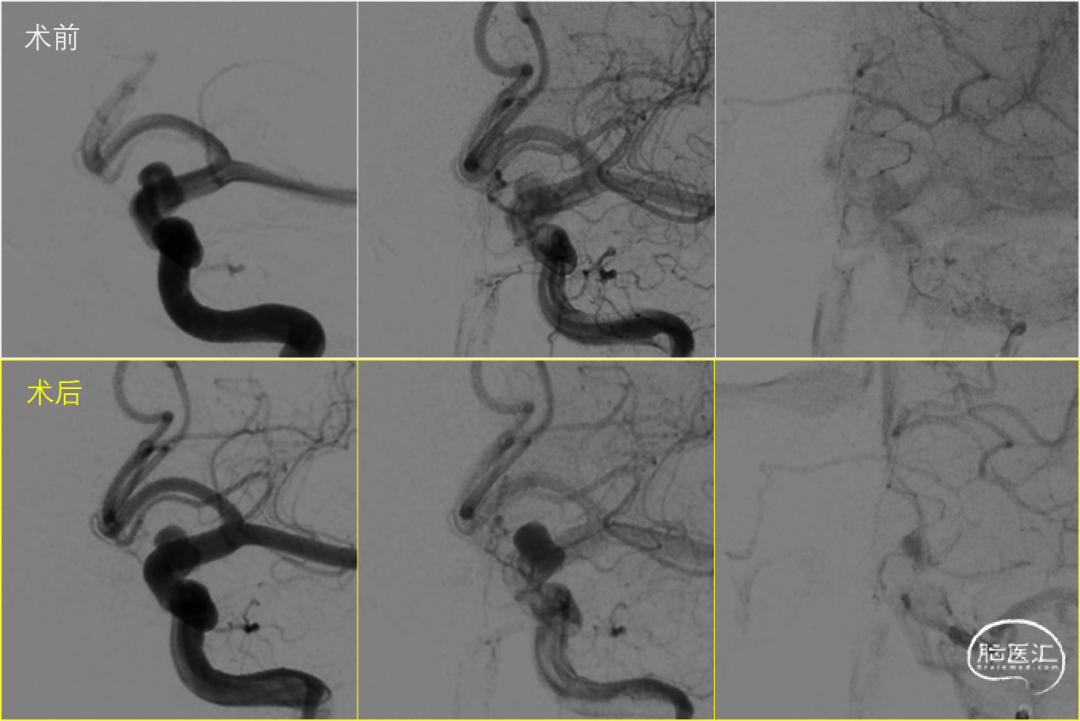

常规通路,经Marksman微导管释放,FD推送顺畅,展开良好(图2)。术后Vaso CT显示各部位贴壁良好(图3)。

图.3

术后即刻造影对比,OKM:A3。